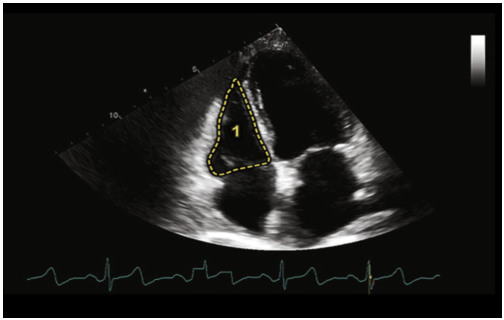

室间隔的厚度测量一般选择胸骨旁长轴切面进行,选择等容舒张期的数值为参考值,可以使用M型超声进行测量以获得更高的精度。为图10所示1区段的数值,其参考值为0.6~1.0 cm。

图片

图10. 室间隔厚度测量示意图